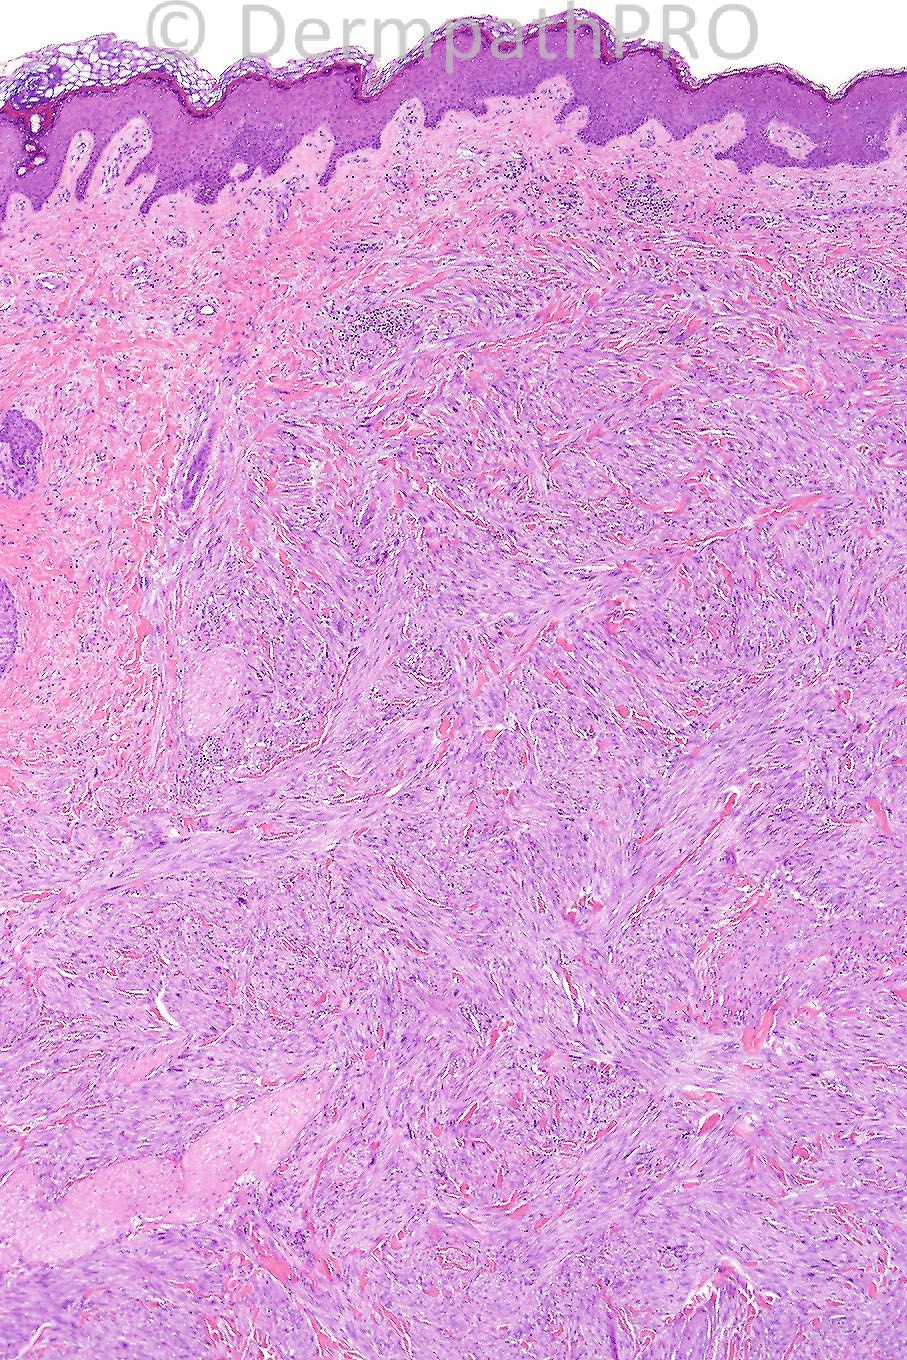

Male 60 years, tumor on leg.

The diagnosis is leiomyosarcoma confirmed with immunohistochemistry. I will be on vacation from tomorrow until August 24th. Iskander will kindly be looking after the spot diagnoses in my absense.

HIGH GRADE SARCOMA. I FAVOUR LEIOMYOSARCOMA. DDx: MPNST; SYNOVIAL SARCOMA (MONOPHASIC); SPINDLED CELL CARCINOMA AND MELANOMA. ONE WOULD REQUIRE IMMUNOHISTOCHEMISTRY TO DIFFERENTIATE BETWEEN THE ABOVE ENTITIES.

High grade spindle cell sarcoma in keeping with Leiomyosarcoma. Immunohistochemistry is required to confirm.